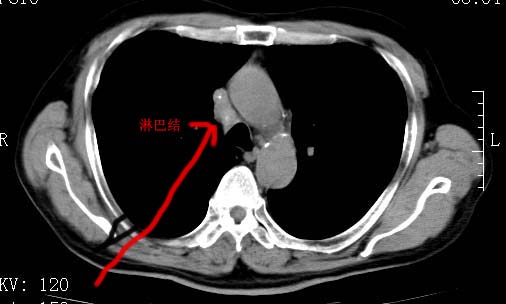

以下是引用zjzjr在2008-6-24 11:19:00的发言:[br]支持左下肺周围型肺癌伴右肺转移,纵隔淋巴结转移,心包积液.

以下是引用zhangling在2008-6-24 14:56:00的发言:[br]我们科室意见报告为[br][br]1考虑左下肺周围型肺癌[br]2右肺小结节考虑转移瘤,纵隔淋巴结转移[br]3心包积液. [br] 各位老师分析的相当好 谢意[br]